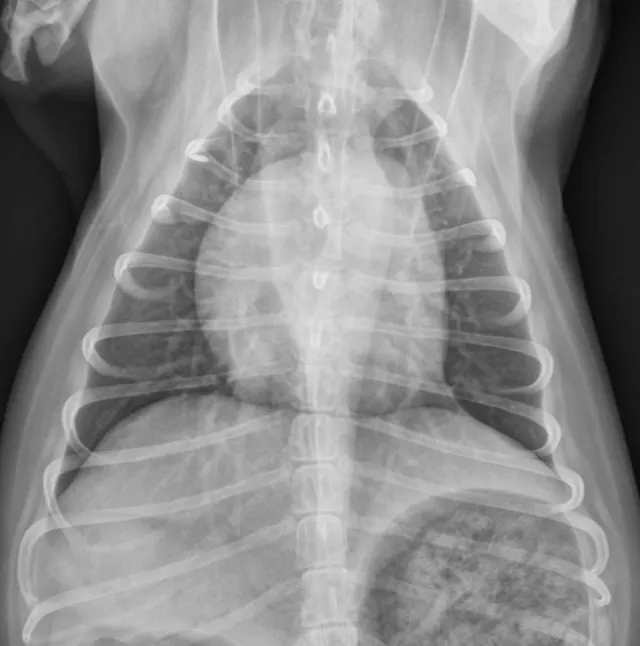

Right lateral (Figures 1 and 2) and dorsoventral (Figures 3 and 4) radiographs of 2 dogs with grade 3/6, holosystolic, left apical murmurs. Dog 1 (Figures 1 and 3) has mild left atrial enlargement; dog 2 (Figures 2 and 4) has a severely enlarged left atrium.